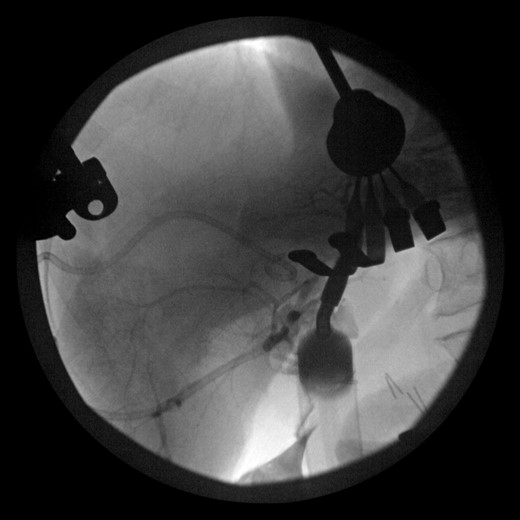

Postoperatively, the patient had persistent high-output bilious drainage. He was discharged on postoperative Day 6 with a drain in place. He returned to the outside facility approximately 4 days later with jaundice, weakness, fatigue and pain. A computed tomography (CT) scan of the abdomen and a nuclear cholescintigraphy scan confirmed a biliary leak with free intra-abdominal fluid consistent with biliary peritonitis (Fig. 1). The patient was transferred to our critical care unit for further management.

CT showing large biloma and intrahepatic biliary dilatation. Percutaneous drain visible in the gallbladder fossa.